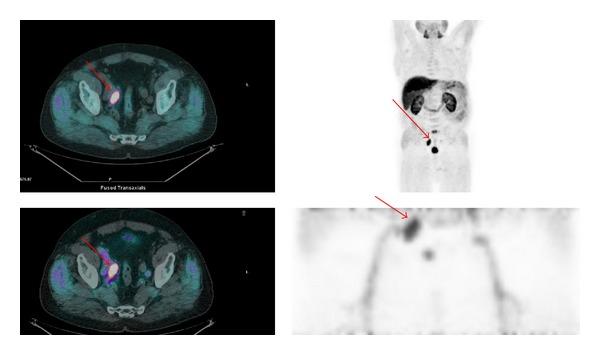

100 consecutive PC patients (mean age 70.5 years, mean PSA 21.35 ng/mL) were prospectively evaluated. New protocol consisted of an early scan of the pelvis immediately after the injection of the tracer (1 bed position of 4 min) followed by a whole body scan at one 1 hour. Early and 1 hour images were compared for interfering activity and pathologic findings.

The overall detection rate of FCH PET/CT was 64%. The early static images of the pelvis showed absence of radioactive urine in ureters, bladder, or urethra which allowed a clean evaluation of the prostatic fossae. Uptake in the prostatic region was better visualized in the early phase in 26% (7/30) of cases. Other pelvic pathologic findings (bone and lymph nodes) were visualized in both early and late images.

Early (18)F-choline images improve visualization of abnormal uptake in prostate fossae. All pathologic pelvic deposits (prostate, lymph nodes, and bone) were visualized in both early and late images.

前瞻性评估了100例连续的前列腺癌患者(平均年龄70.5岁,平均前列腺特异性抗原21.35 ng/mL)。新方案包括在注射示踪剂后立即对骨盆进行早期扫描(1个床位,4分钟),随后在1小时后进行全身扫描。比较早期和1小时图像的干扰活性及病理结果。

FCH PET/CT的总体检出率为64%。骨盆的早期静态图像显示输尿管、膀胱或尿道无放射性尿液,从而可以清晰地评估前列腺窝。在26%(7/30)的病例中,早期前列腺区域的摄取情况显示得更好。其他骨盆病理结果(骨骼和淋巴结)在早期和晚期图像中均可见。

早期(18)F-胆碱图像可改善前列腺窝异常摄取的可视化。所有骨盆病理沉积物(前列腺、淋巴结和骨骼)在早期和晚期图像中均可见。